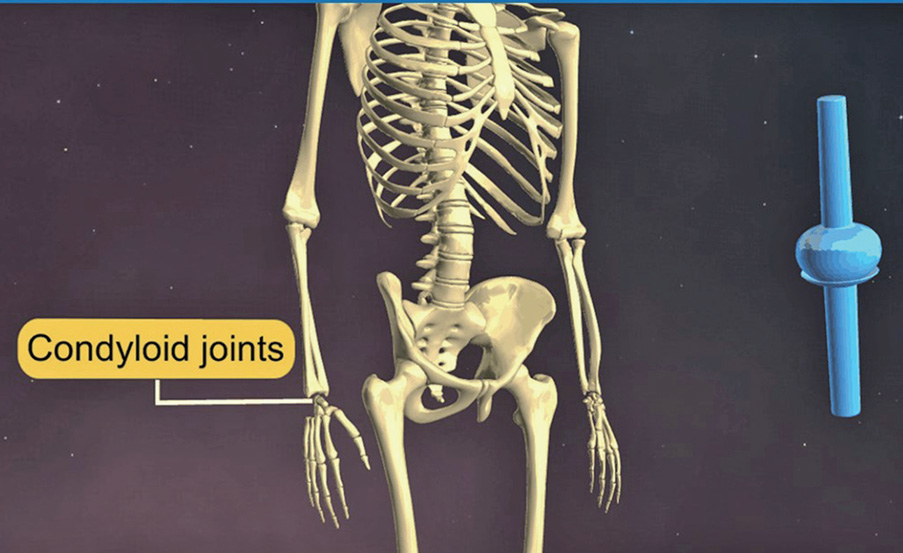

- 가동관절④ 융기관절